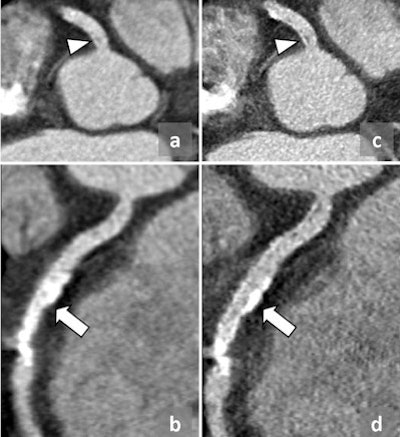

Patient weight is related directly to the scan quality, and the heavier the patient, the greater is the likelihood that the scan will be of poorer quality, Stirrup noted. Diagnostic accuracy is reduced in obese patients because the scan beam is significantly more attenuated as a result of increased tissue between the tube and the detectors; this is especially important when looking at small vessels. Image quality in patients who have a lot of calcium also may be reduced, particularly if narrowing of the vessels is under investigation. He advocates using beta-blockade to improve image quality for all patients regardless of CT scanner technology. Scanning those who have poorly controlled atrial fibrillation often results in a poor-quality image and such patients are often better served by an alternative imaging technique.

To improve image quality in overweight patients, tube voltage can be increased to boost beam energy, but this is limited by the amount of energy that can be put through an x-ray tube. For contrast issues, Strirrup suggests higher flow rates or stronger contrast agents may be more suitable for overweight patients.

To obtain the single heartbeat acquisition scan needed, he suggests using a large cannula needle that will allow fast flow rates for injection of contrast medium. The right antecubital fossa is the preferred place for placing the cannula because the contrast reaches the heart without crossing the aortic arch, reducing the chance of streak artifacts.